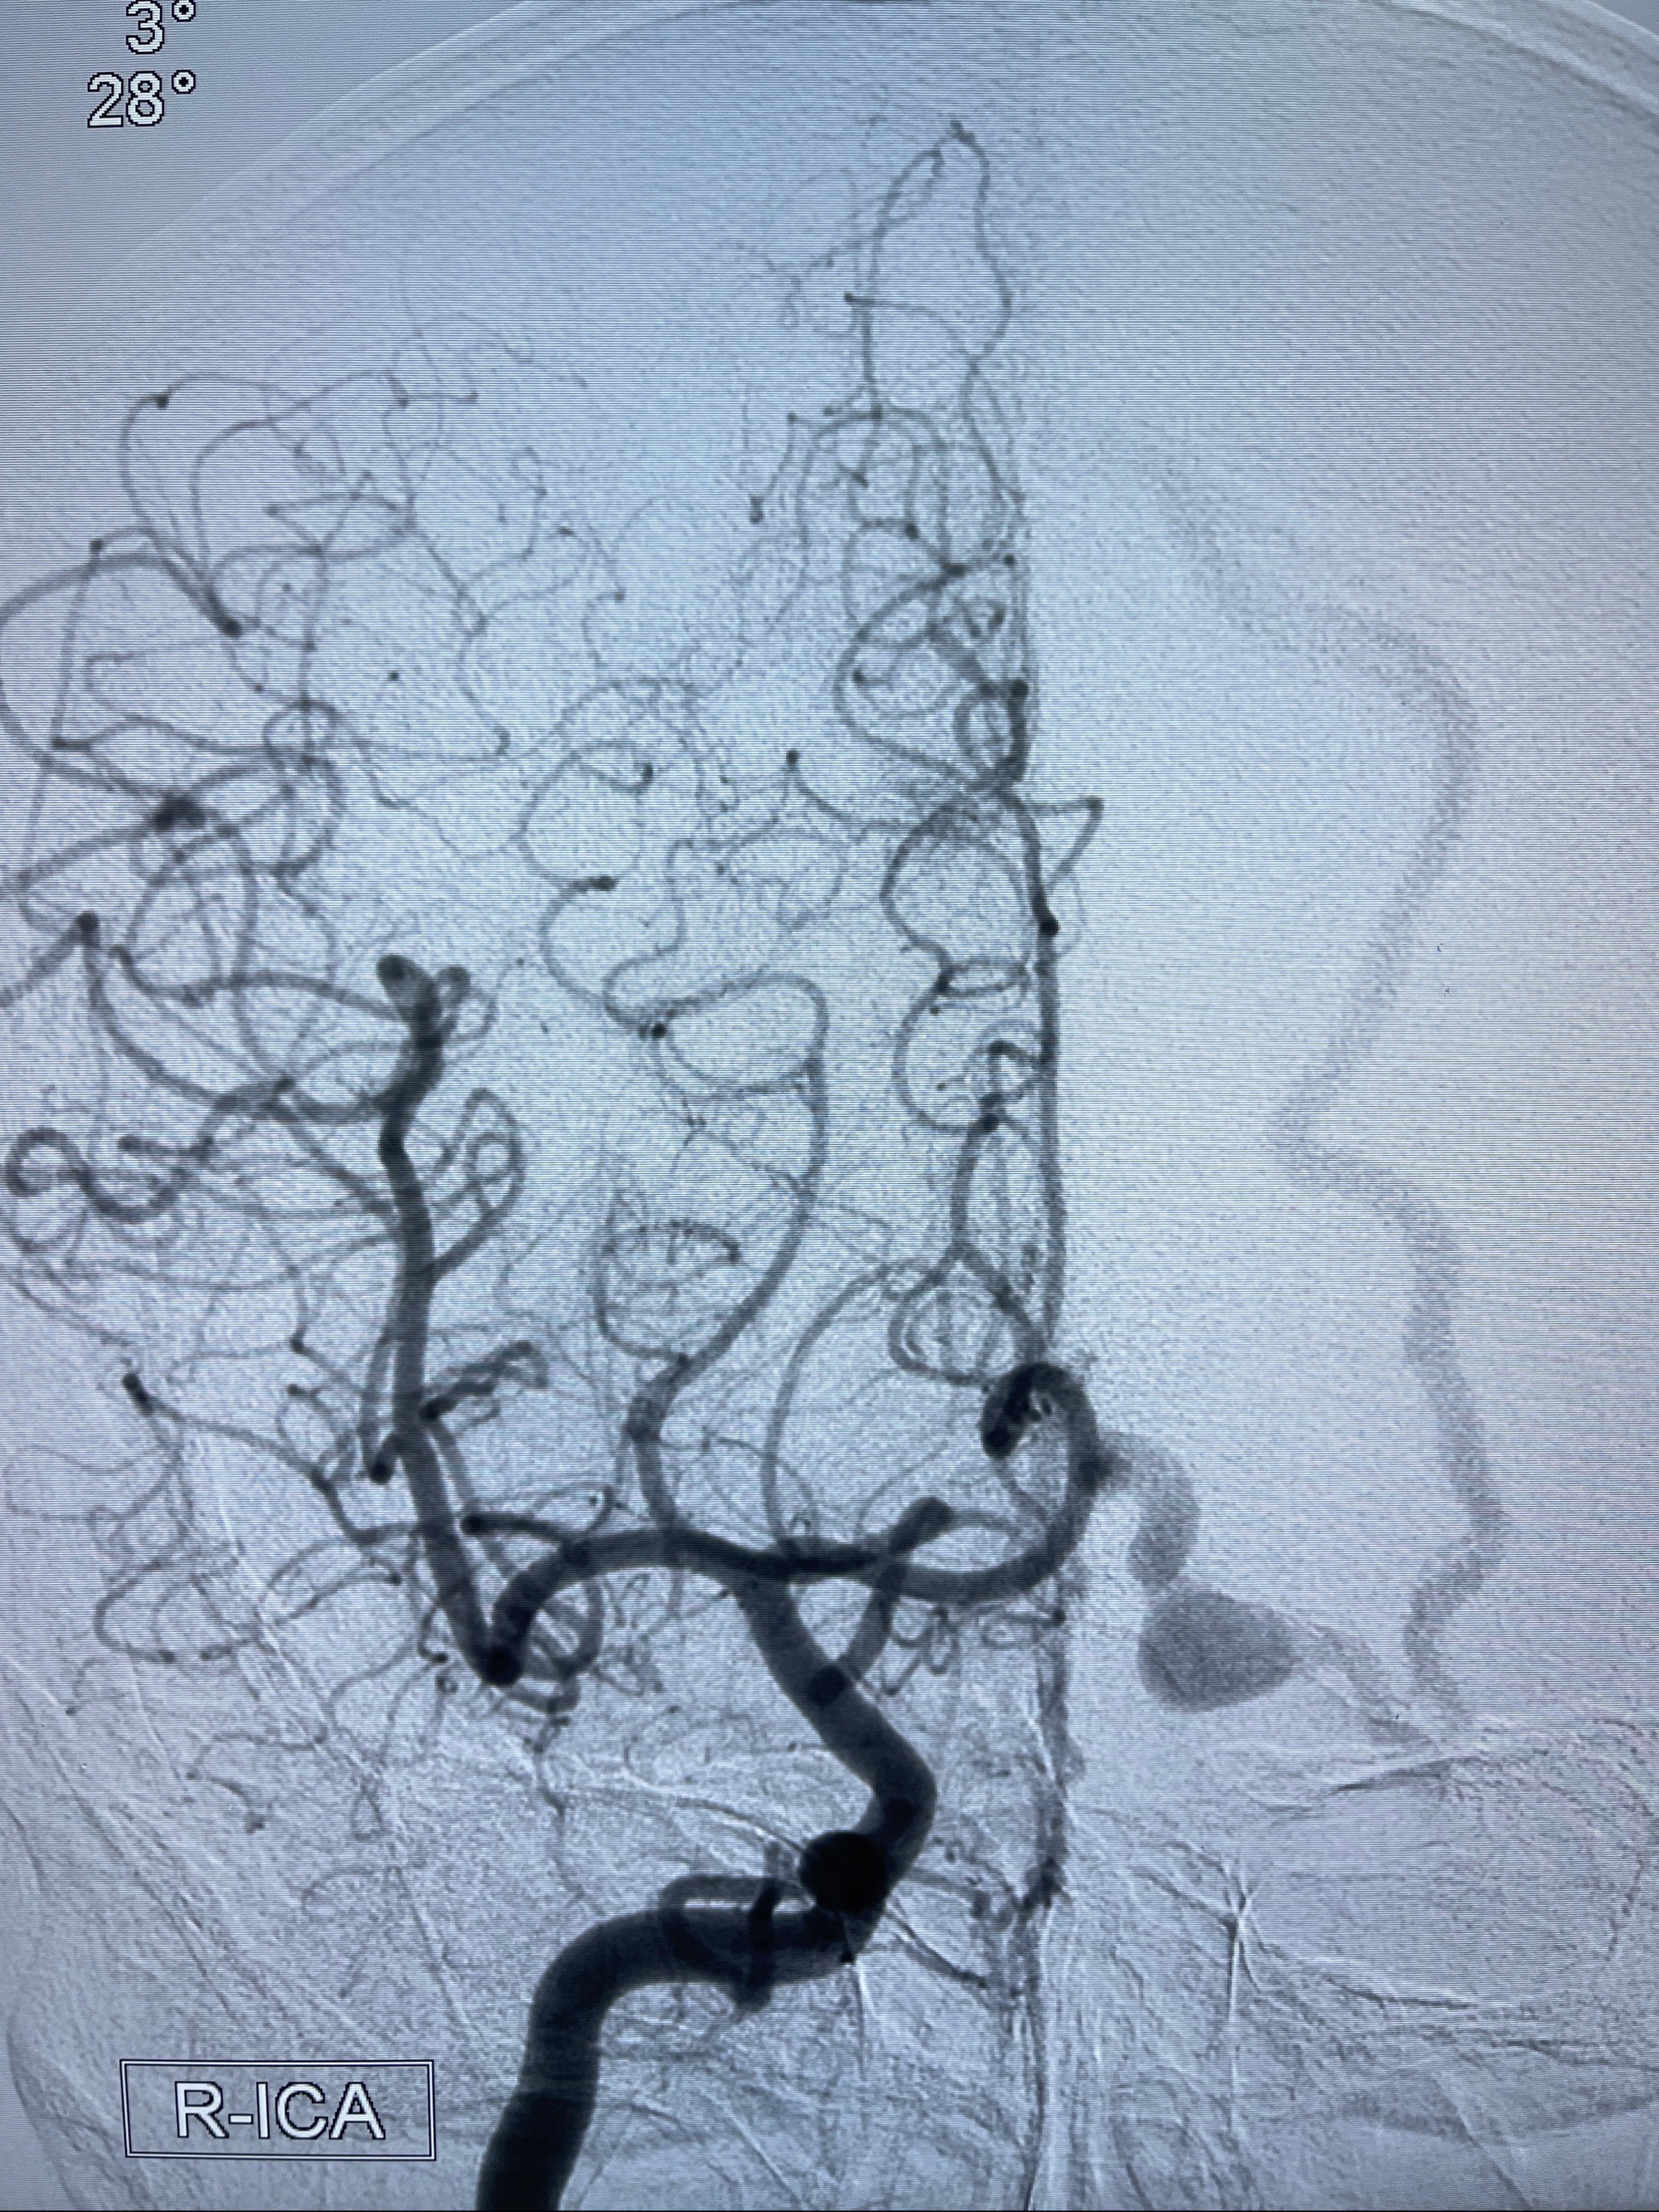

2023年8月21日]景德镇市第一人民医院脑血管造影检查,提示:主动脉弓、双侧颈总动脉、锁骨下动脉造影未见异常,左侧大脑前动脉静脉瘘。

2023-09-13全脑血管造影:前颅底硬脑膜动静脉瘘,供血动脉为双侧胼周动脉、眼动脉脑膜支,静脉向上矢状窦方向引流